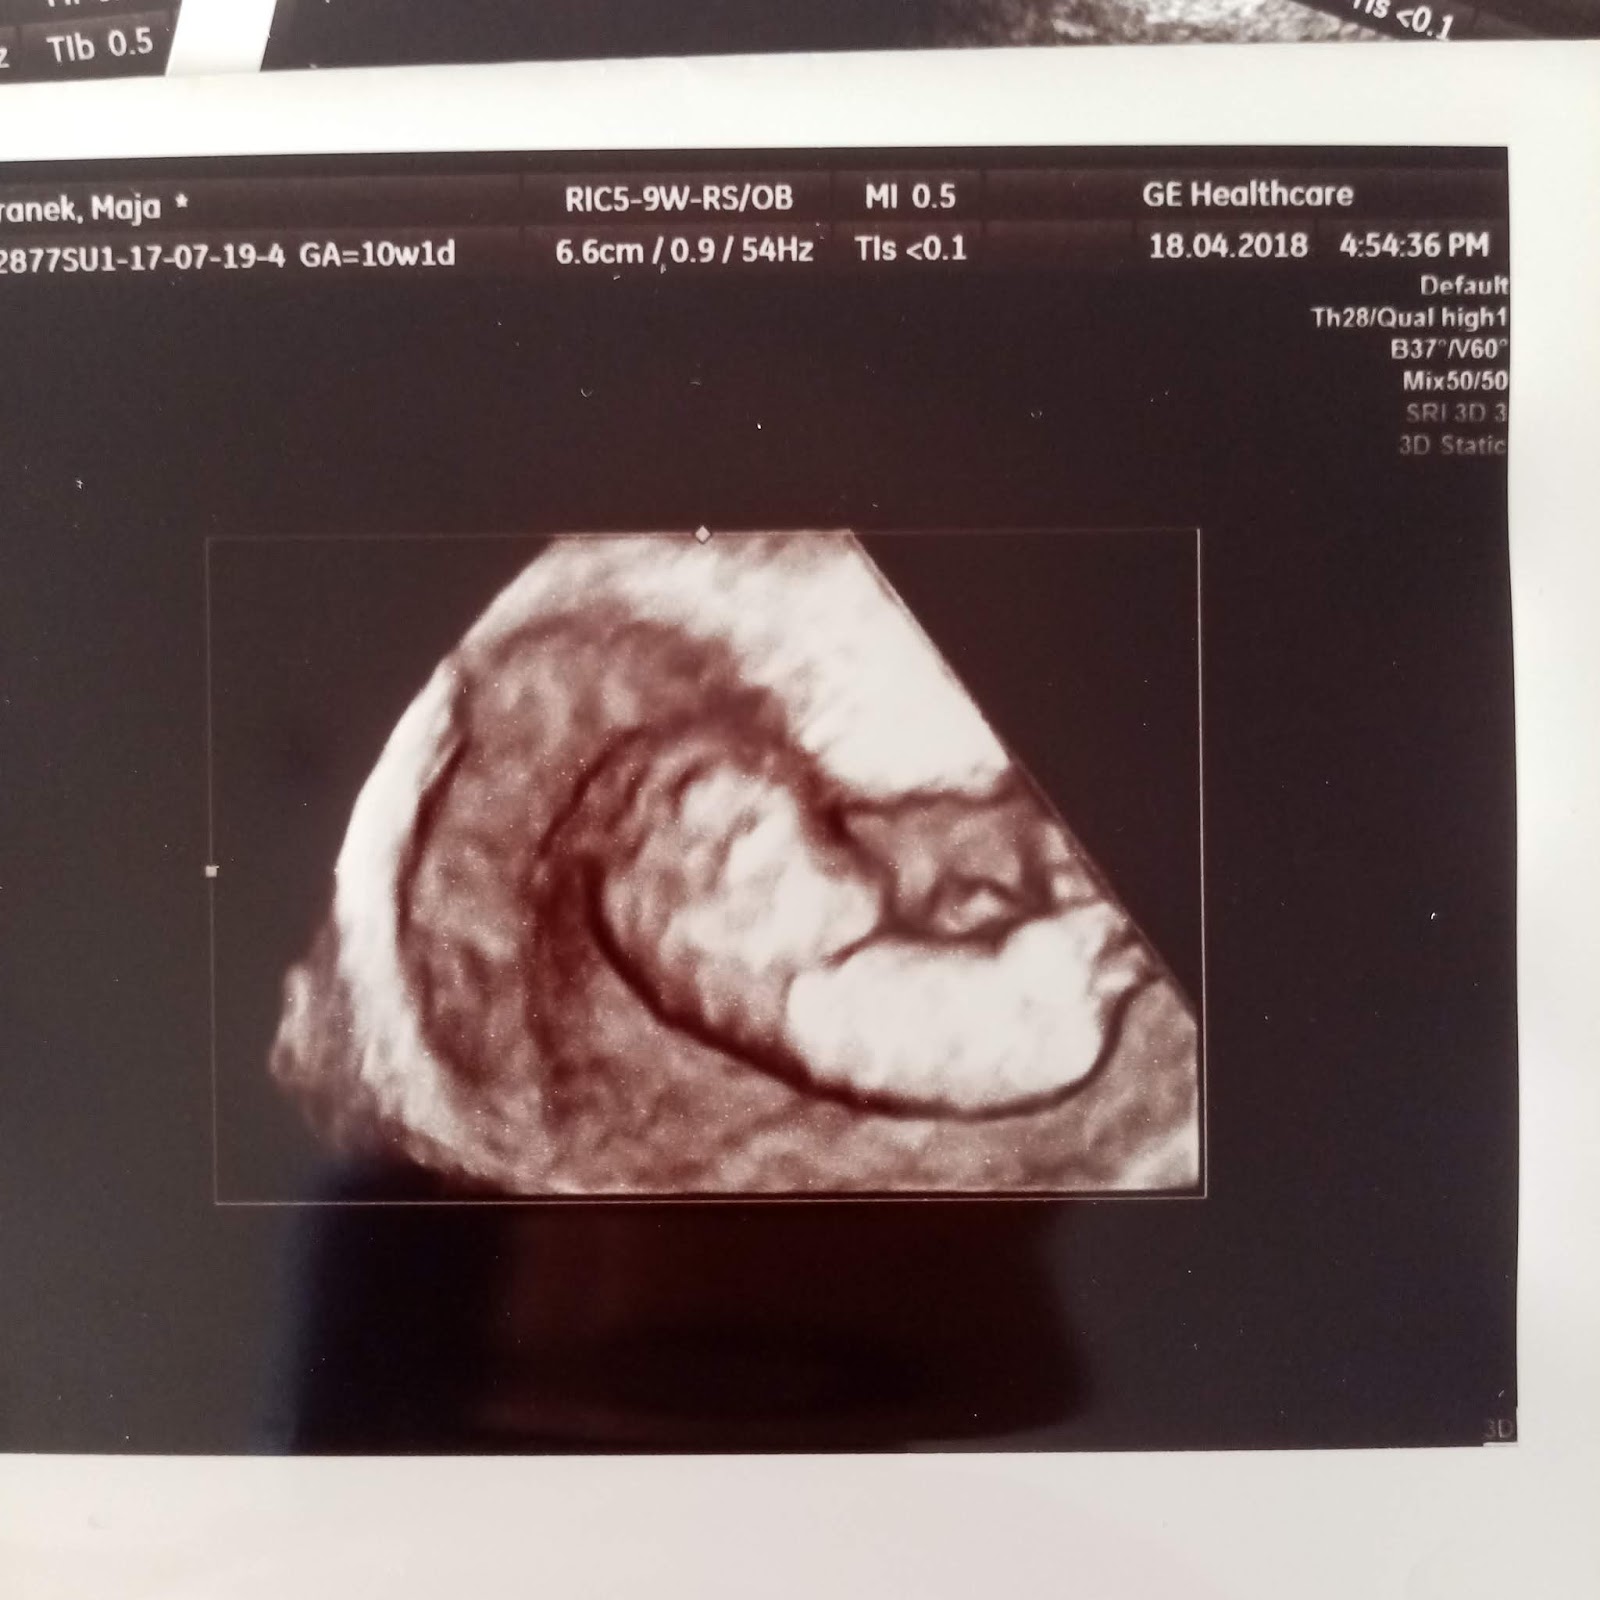

Maluszek miał zrobione pierwsze zdjęcia 3D, które mnie rozczuliły, bo był na nich taki we mnie wtulony.

Urósł prawie 2 krotnie do 3,08 cm i jego serduszko 180 uderzeń na minutę.

Podczas 3 usg prenatalnego gin sprawdził wszystkie narządy, szczególnie skupił się na budowie serduszka i mózgu, a także innych narządów, ale serduszko mogliśmy dłużej posłuchać.

Zrobił też śliczne zdjęcia 3D. Wtedy nawet nie podejrzewałam, że to będzie moja ostatnia wizyta u niego i ostatnie usg.